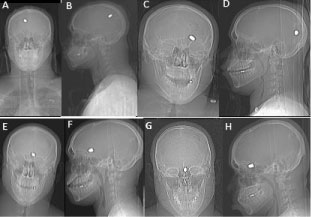

Repeat CT four days later after a single episode of seizure revealed bullet migration posteriorly, likely gravity directed within the injury track in the bed-ridden patient. Within the bullet tract, there is significant interval ballooning of intraparenchymal hemorrhage involving the medial posterior left frontal lobe and left parietal lobe. Three days later (one week after initial injury) the bullet has moved anteriorly appearing next to the left ventricular atrium (Figure 2). Two weeks later on initial follow up the bullet appeared in the anterior margin of the cistern of the lamina terminalis, along the medial surface of the left frontal lobe next to the frontal horn of the left lateral ventricle (Figure 3). Two weeks later (one month after initial injury) the bullet migrated medially and downwards, lodged in the left paramedian anterior cranial fossa floor under the left gyrus rectus, superior to the posterior cribriform plate margin (Figure 4). The patient was conscious with a right hemianopsia but no other eloquent neurologic deficit, even after his single seizure episode. The patient was discharged from the hospital after one month of observation. Surgical intervention was not considered, as the patient displayed no new neurological deficit during the follow-up. He was managed conservatively, no recurrent seizures reported. As he remained asymptomatic, continued conservative observation of this bullet was recommended. However, if he does have symptoms, including visual disturbances or uncontrollable seizures, and the bullet appears to be stable in position, retrieval may be an option in the future if he is symptomatic. He is now doing well and has made a great recovery (Figure 5 and Figure 6).

Figure 6: RX showing the position of the bullet. A) First day front; B) Sagittal projection; C) One week front; D) Sagittal projection; E) Two weeks front; F) Sagittal projection; G) One month front; H) Sagittal projection. View Figure 6